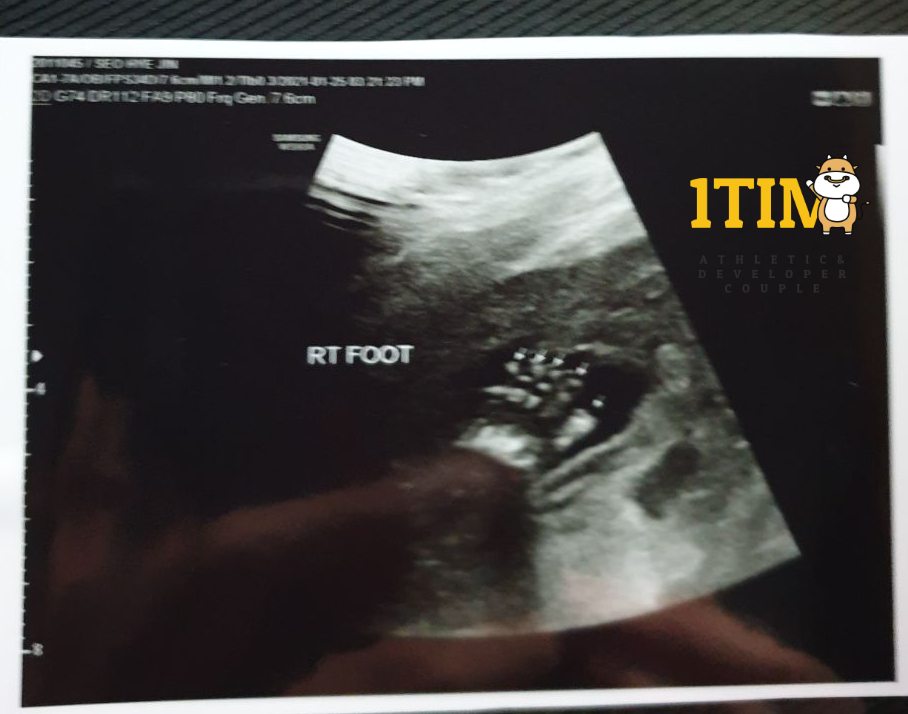

2021. 1. 25. (21주 4일)

오늘은 한달만에 정기검진이 있는날. 정밀 초음파가 예정되어 있다.

양손가락/양발가락 갯수, 양쪽 귀, 입술, 코가 잘~~~ 붙어있는지 확인했다.

물론 정상 ~ 키키키 대견하구나.. 크롱군..

태아 몸무게 : 460g (21w4d)

이제는 키 대신 몸무게와 머리둘레로 태아의 성장을 확인하는 시기